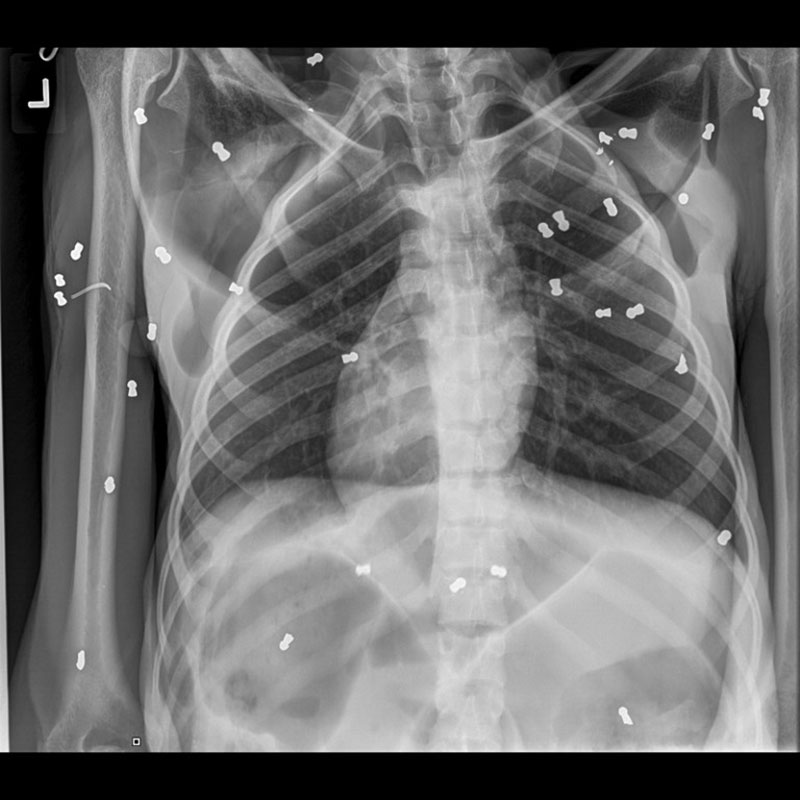

ด้าน เยนนี สรัสวาตี สัตวแพทย์ผู้ทำการผ่าตัด เผยว่า อุรังอุตังตัวแม่ที่ทีมช่วยเหลือตั้งชื่อว่า "โฮป" ได้รับบาดเจ็บจากการถูกกระสุนปืนลมยิงใส่ไม่ต่ำกว่า 74 นัด ภาพกระสุนที่ฝังอยู่ในตัวของมันสามารถมองเห็นได้อย่างชัดเจนจากภาพเอกซเรย์ โดยมี 4 นัด ฝังอยู่บริเวณตายซ้าย และ 2 นัดฝังอยู่ที่ตาขวา นอกจากนี้ตามตัวของเจ้าโฮปก็ยังมีบาดแผลจากการถูกวัตถุแหลมคมทำร้ายด้วย

ขณะนี้ เจ้าโฮปได้รับการผ่าตัดเพื่อนำกระสุนออกแล้ว 7 นัด

และแพทย์ก็ได้ทำการรักษากระดูกไหปลาร้าที่หักให้